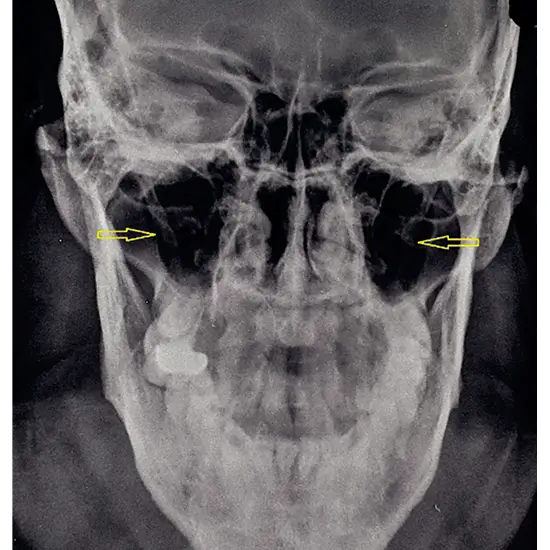

The Townes View X-Ray test is used to examine the inside of the skull. This examination examines the anterior external area of the skull where the rays enter the brain from front to back. After an accident or trauma, a doctor may order this test to see inside the skull.

• To identify skull fracture following an accident or trauma

• To identify the existence of any brain cancer, tumor, or cyst (extra lesion, mass growth).

• To determine the displacement of the brain's sutures and joints.